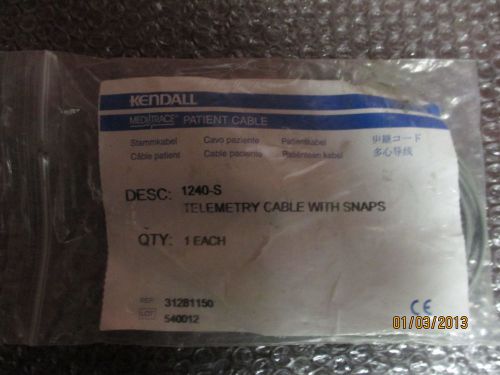

Lot of 2 Kendall 1240-s 4 Lead Telemetry Patient Cable with Snaps